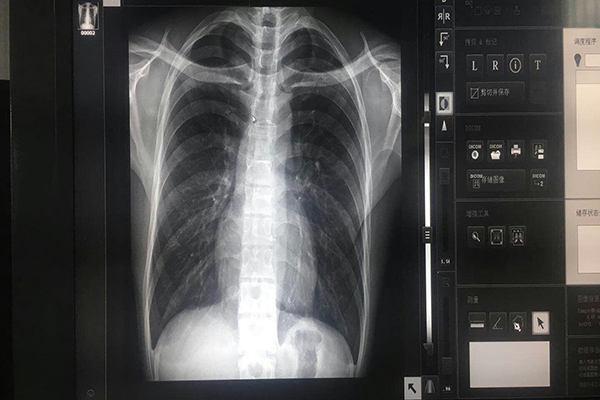

單位面積內(nèi)實(shí)際顯示像素的數(shù)量,如800600、12001600等。普通顯示器有:1024768,12801204;基本上是橫屏顯示,不需要橫/豎屏轉(zhuǎn)換;醫(yī)療灰階顯示器有:根據(jù)影像的需要,可以橫/豎屏轉(zhuǎn)換,10241280(豎屏)/12801024(橫屏),稱為1百萬(wàn)像素(1MP),常用橫屏顯示, 多適用于CT、MRI、數(shù)字胃腸機(jī);12001600(豎屏)/16001200(橫屏);稱為2百萬(wàn)像素(2MP),簡(jiǎn)稱1K,常用豎屏顯示, 多適用于CR、DSA、數(shù)字胃腸機(jī)、,PACS閱片工作站;15362048(豎屏)/20481536(橫屏);稱為3百萬(wàn)像素(3MP),簡(jiǎn)稱1.5 K,常用豎屏顯示, 多適用于CCD-DR、PACS診斷工作站;20482560(豎屏)/25602048(橫屏);稱為 5 百 萬(wàn)像素( 5MP ),簡(jiǎn)稱 2 K ,常用豎 屏顯示,多適用于平板DR、乳腺機(jī)、PACS診斷工作站;醫(yī)療灰階顯示器的分辨率與價(jià)格成正比,與放射設(shè)備的分辨率正相關(guān),相應(yīng)的設(shè)備應(yīng)當(dāng)配套相應(yīng)分辨率的顯示器。